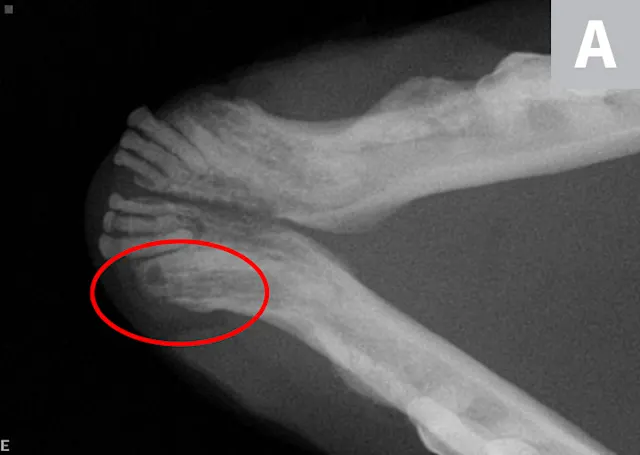

The patient periodically pawed at her face and shook her head. Oral examination revealed unhealed extraction sites with visible protrusion of tooth fragments through the gingiva (Figure 1). The areas were inflamed, and purulent exudate was present in the open alveolus of the right mandibular canine tooth (Figure 2; see Tooth Numbering).

FIGURE 1

Intraoral image of the left maxillary canine revealing inflammation and a tooth fragment (arrow) extending into the oral cavity